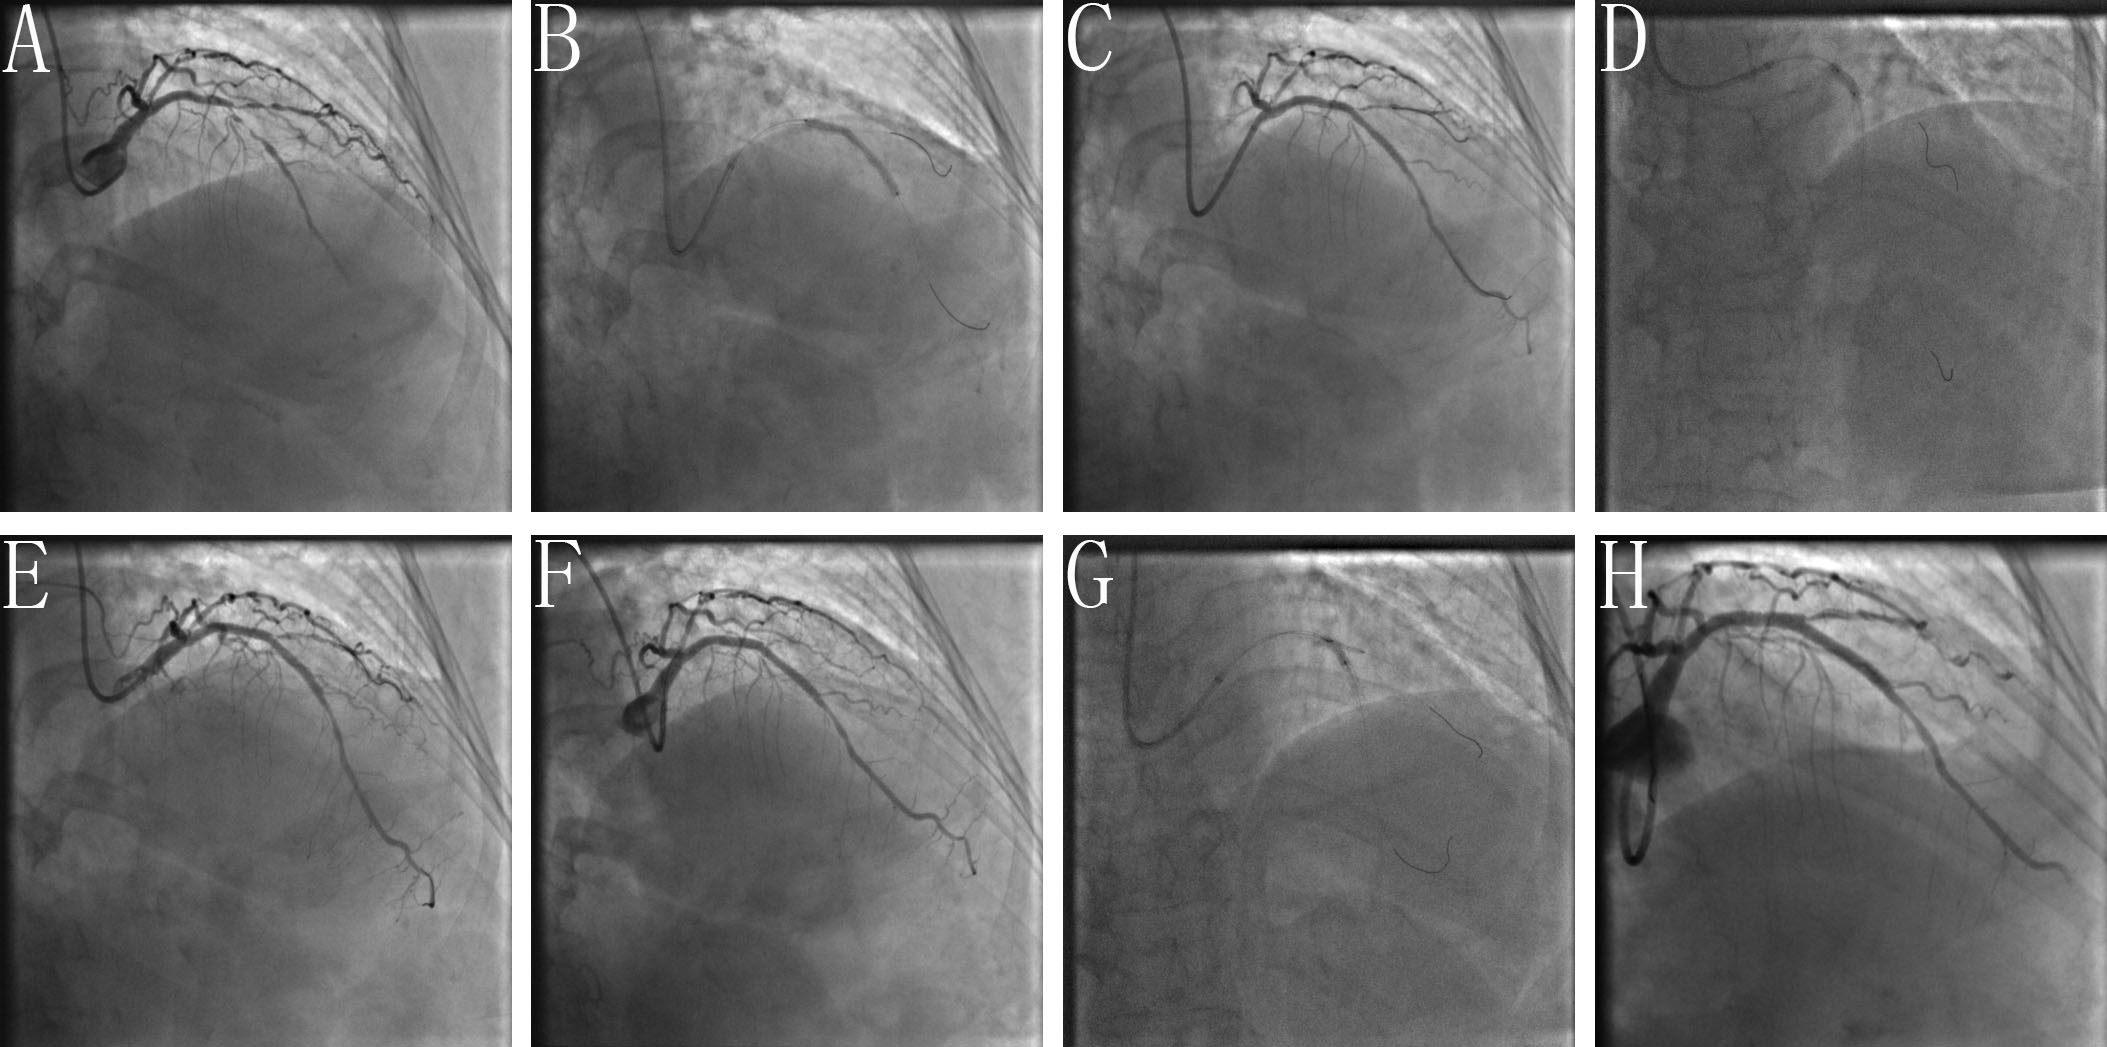

POTA: Briefly, after MV stenting, at least one of the POTAs (e.g., POT-alone, POT-S-POT, POT-K-POT) were used at the discretion of the operators. A clinical example and final results using the BOOT and POTA for treating an unstable angina patient with a severe LAD-D1 TCBL are shown by coronary angiography in Figs. 2,3, respectively.

Fig. 2.Clinical practice of the BOOT technique. (A) Baseline angiogram with significant stenosis of the left anterior descending (LAD)/first diagonal bifurcation (D1) (medina classification: 1, 1, 1). (B) SBSD: pre-staying a compliance balloon in the D1 with its proximal maker in the bifurcation core and then properly positioning of the LAD stent. (C) SBSD: First inflating the D1 balloon and then stent balloon, followed by first deflating the stent balloon and then D1 balloon. (D) Snuggling balloon-stent dilation. (E) After rewiring the SB closest to the carina withdraw the pre-imbedding D1 balloon and guidewire, then placing 2 non-compliance balloons with mini-juxtaposition or snuggling-position in the bifurcation core. (F) Sequentially inflating the SB and MB balloons with simultaneous deflation. (G) Finalizing the procedure with (re)-POT. (H) Final angiogram result.